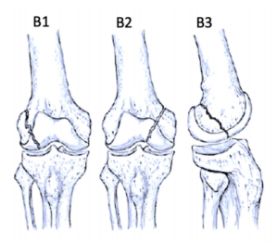

AO/OTA Classification

• Type B: Partial articular fractures

ao-classification-distal-femur-type-b